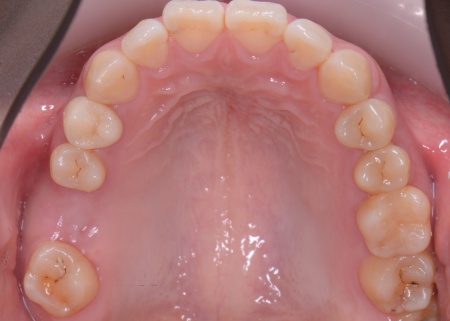

20代女性 歯の根が割れた歯を抜歯したあと矯正治療と骨再生を併用したインプラント治療で補った症例

また、上下の歯を噛み合わせた際に前歯が噛み合わず隙間ができる開咬(かいこう)と呼ばれる噛み合わせも見られました。

開咬は奥歯に負担が集中しやすく、その影響で今回のように歯の根が割れてしまった可能性が高いと考えられます。

まず、右上と左下の奥歯を抜歯しました。

その後、全体の噛み合わせを改善するため、矯正治療を開始しています。